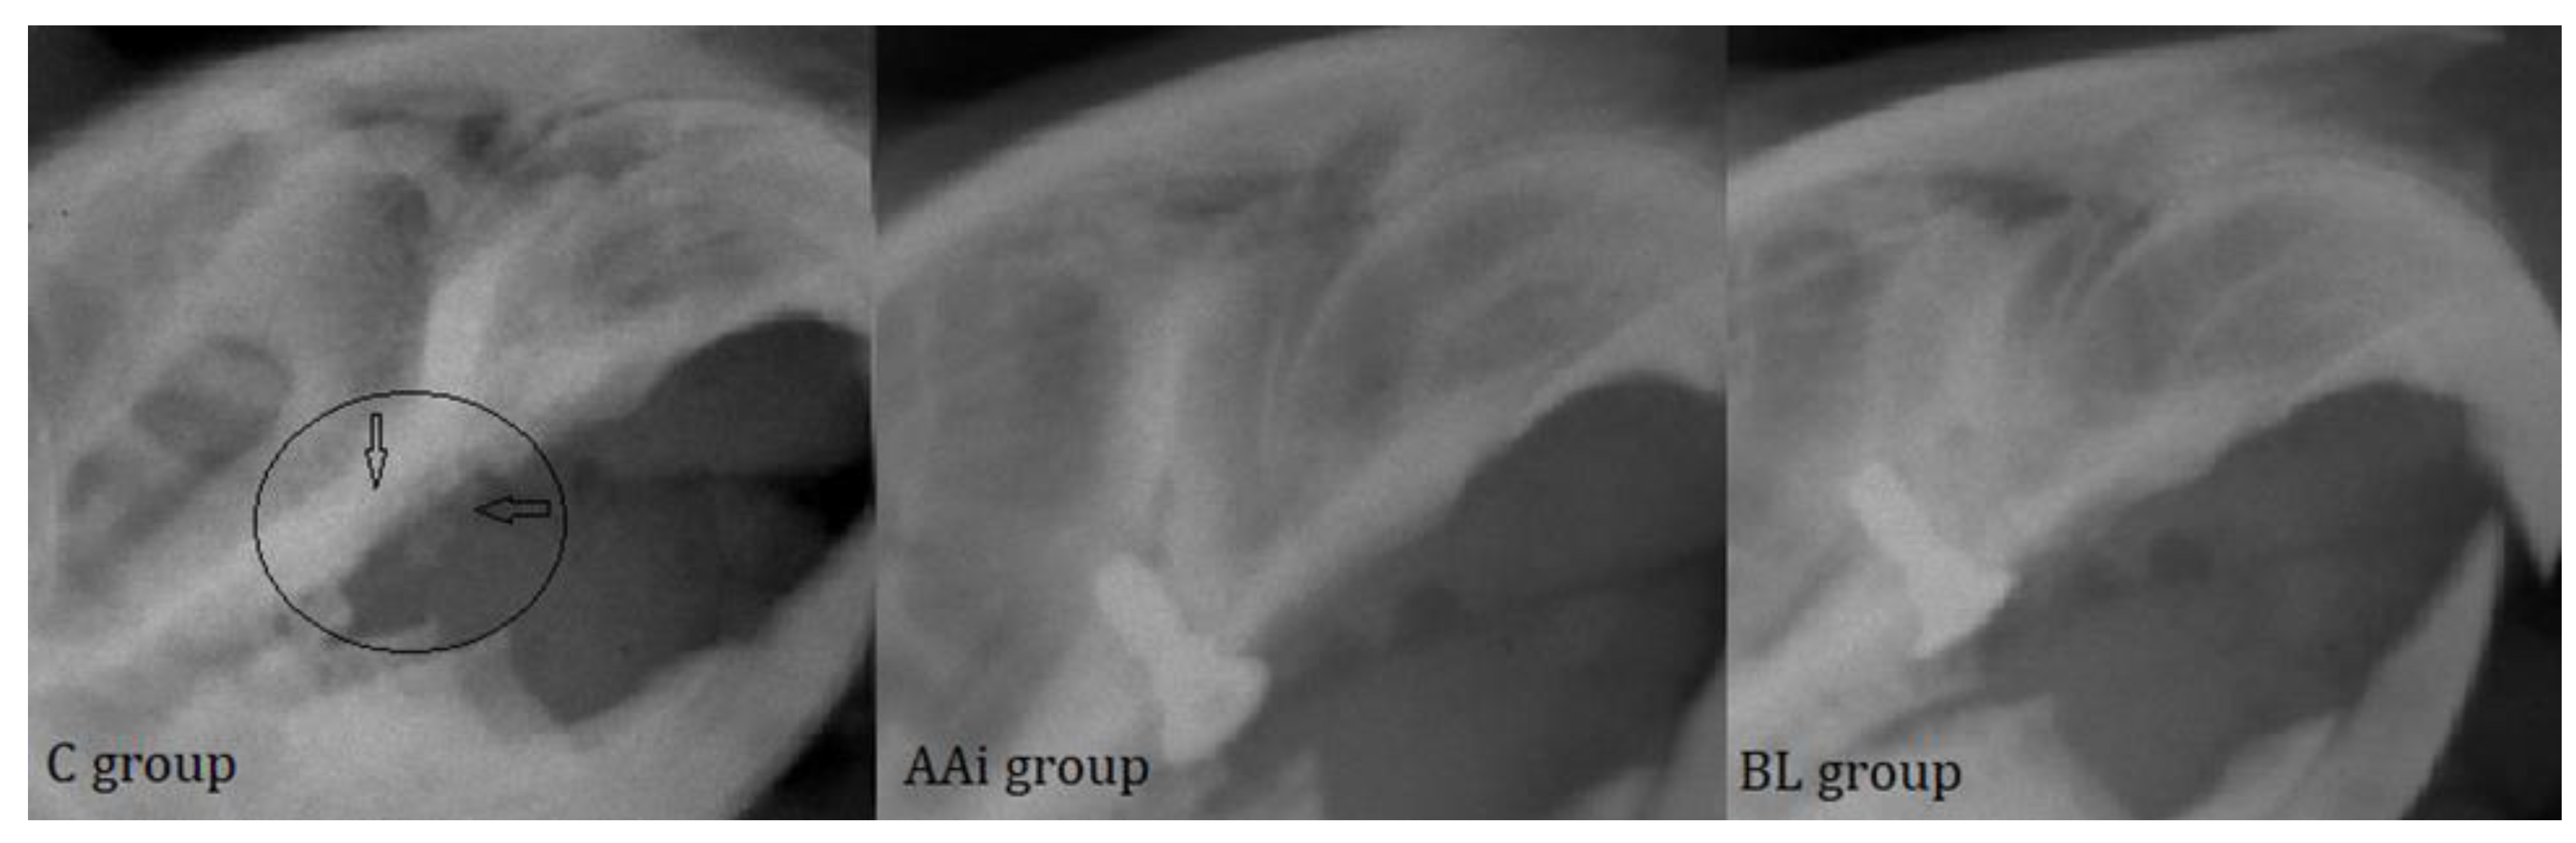

Dental X-rays are an integral part of the assessment of peri-implant disease for patients with clinical evidence of tissue destruction around teeth and/or implants. A careful review of the current approach to PI diagnosis shows that radiographs inform only a small proportion of the condition. The area in peri-implant assessment where radiographs play a key role, however, is in treatment planning, making it possible to observe outcomes after curative measures have been instituted. Following radiological examination, in the control groups, where we did not find the implanted devices, we could observe a high level of bone resorption, with a widened aspect of the bone socket (Figure 6, black arrows). In animals treated with antibiotics or bacterial lysate, the implants showed a correct position in the bone and optimal osseointegration (Figure 6).

Radiological examination, as an integral part of PI diagnosis, helped establish implant integrity throughout this study. Through it, the level of bone density was compared, and in the control groups, this density was much lower (also revealed by the degree of survival of the implants) than in the antibiotic- and bacterial lysate-treated groups. An analysis of the obtained images revealed optimal osseointegration in the implants and bone densities characteristic of reduced inflammatory processes.

Figure 6. The radiological appearance of bone support after implant loss where resorbed bone can be seen, with irregular edges (circle and black arrows) in C group and implants in groups AAi and BL at the end of the study.